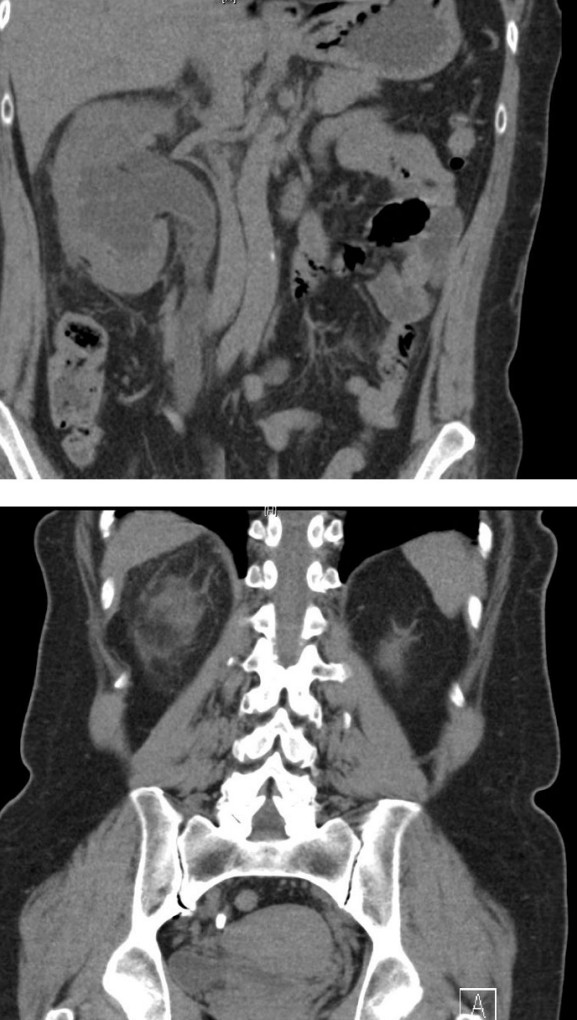

Penetrating back injury with renal trauma

A 35-year-old man sustains a single stab wound to the left side of his back. The incoming ambulance team have …